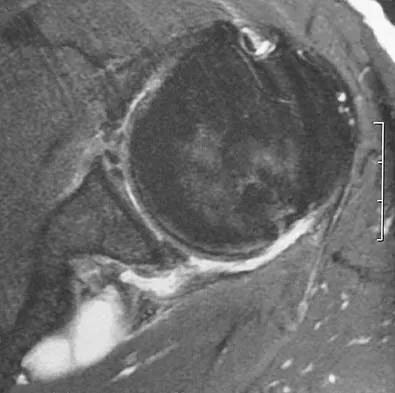

A 28-year-old man reports knee stiffness, swelling, and a constant ache that is worse with activity. Examination reveals an effusion, global tenderness, and warmth to the touch. Flexion is limited to 110 degrees. Figures 48a through 48d show sagittal T1-weighted, sagittal T2-weighted, axial T1-weighted fat-saturated gadolinium, and axial gradient echo MRI scans. Based on these findings, what is the most likely diagnosis?

Explanation